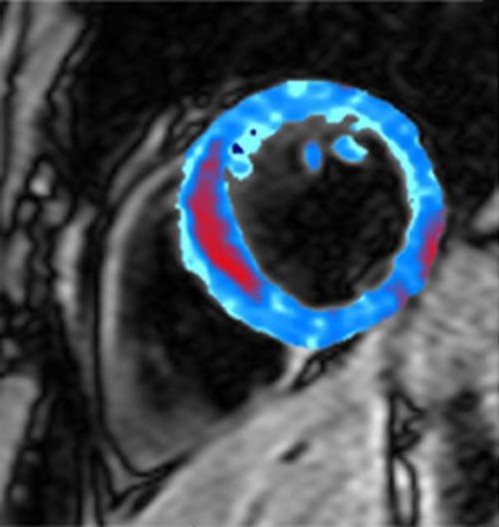

新浪科技讯 北京时间1月22日消息,据美国生活科学网报道,英国医生首次拍到心脏病发作后心肌内部出血的照片。发表在1月19日《放射线学》杂志上的一份研究报告指出,心肌出血量可反映人们心脏病发作后心脏的受损程度。

在这项最新研究中,研究人员使用核磁共振成像检查了15名刚经历心脏病发作的患者的心脏内部出血情况。通过血液中的铁的磁效应研究人员能看到出血的范围。图像显示,与心脏病病情相对较轻的人相比,那些心脏病病情较重,心肌受损较大的患者心肌出血更多。该研究的第一研究人员、伦敦帝国学院英国医学研究委员会临床研究科学中心的迪希伦·奥里根说:“这一研究让我们对心脏病造成的损害有了新的理解。使用这种新的扫描技术,我们得知受损心肌内部出血的患者康复的概率较小。”